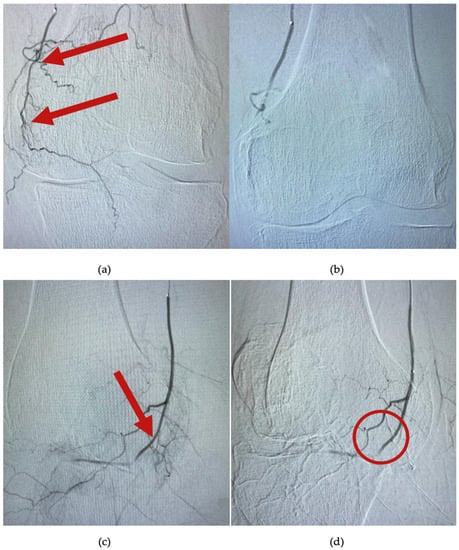

The procedure begins with the catheterization of the left brachial artery and the placing of a 5Fr catheter at the level of the superficial femoral artery. Afterwards, a selective catheterization of the superior genicular arteries (medial or lateral) is performed by using a 0.021 inch microcatheter (Direxion, Boston Scientific, Marlborough, MA, USA). Under fluoroscopic guidance, the desired genicular artery branch is identified. In total, 200 mcg of nitroglycerine is injected, and the knee is immediately iced for 10 min by using an instant cold pack of ice (Dynarex, Blauvelt, NY, USA). Then, an angiogram reveals hypervascularity with numerous capillary branches within the medial or lateral joint space, as exemplified in Figure 3a,c. A suspension with contrast substance and imipenem/cilastatin sodium (IPM/CS) (embolic agent) was injected. Distal hypervascularity was assessed fluoroscopically until it was resolved. As seen in Figure 3b,d, adequate blood flow should be maintained within the selected artery branch after deployment. A control angiogram is performed as a final step, and hemostasis is achieved by manual compression of the brachial artery. All patients were scheduled to be discharged 4 h postintervention.

Figure 3.

Angiogram at the level of the superior medial genicular artery. (a,c) are images of arterial blush (arrows), before embolization; (b) shows complete embolization and lack of the hypervascularity; and in image (d), bone and capsular branches are selectively avoided (circle).